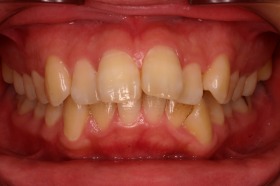

ご覧の症例は出っ歯を矯正治療でキレイにしたケースです。

ご覧の矯正歯科治療の場合は、抜いて矯正歯科

治療していますが東京世田谷矯正歯科センターでは

非抜歯矯正歯科治療をベースにしています。

どうしても抜かないとキレイにならない場合のみ

抜歯して矯正歯科治療しています。